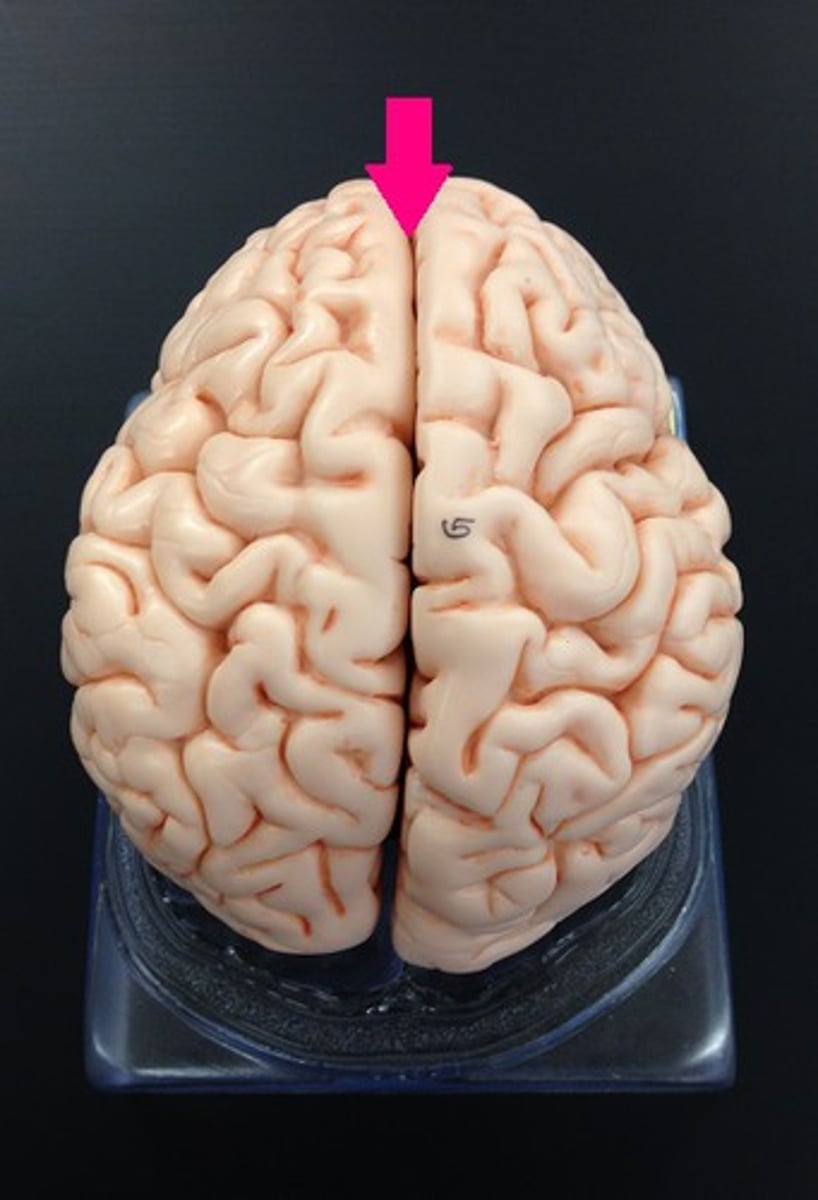

longitudinal fissure

separates cerebral hemispheres

central sulcus

precentral gyrus

frontal lobe

lateral sulcus

post central gyrus

pareital lobe

occipital lobe